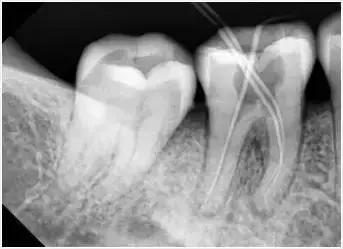

3、确定根管工作长度

应用平行投照X光方法、根管长度测量仪确定根管长度,较 好插针拍X片。